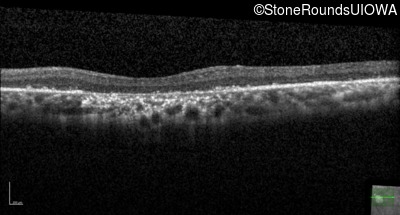

The clinical features supporting the diagnosis of Bardet Biedl syndrome in this patient include: bone-spicule-like pigmentation, narrowed arterioles and macular atrophy on ophthalmoscopy; photoreceptor loss on OCT; ulnar polydactyly, obesity, abnormal cognition, hypertension; and, normally sighted parents.